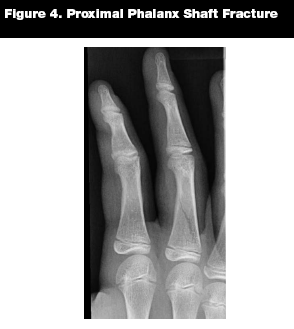

Proximal and middle phalanx fractures are managed similarly.19 (See Figure 4.) Stable fractures that are not displaced can be treated with buddy taping and early range of motion.14 Displaced fractures may be treated with closed reduction and splinting; if this fails, surgical treatment may be needed.14,18 It should be noted that some authors prefer splinting over buddy taping in pediatric fractures.13